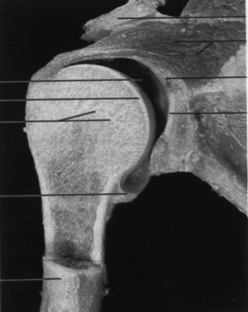

图4-5-8 肩关节韧带(囊外韧带)

图4-5-9 髋关节内股骨头韧带(囊内韧带)